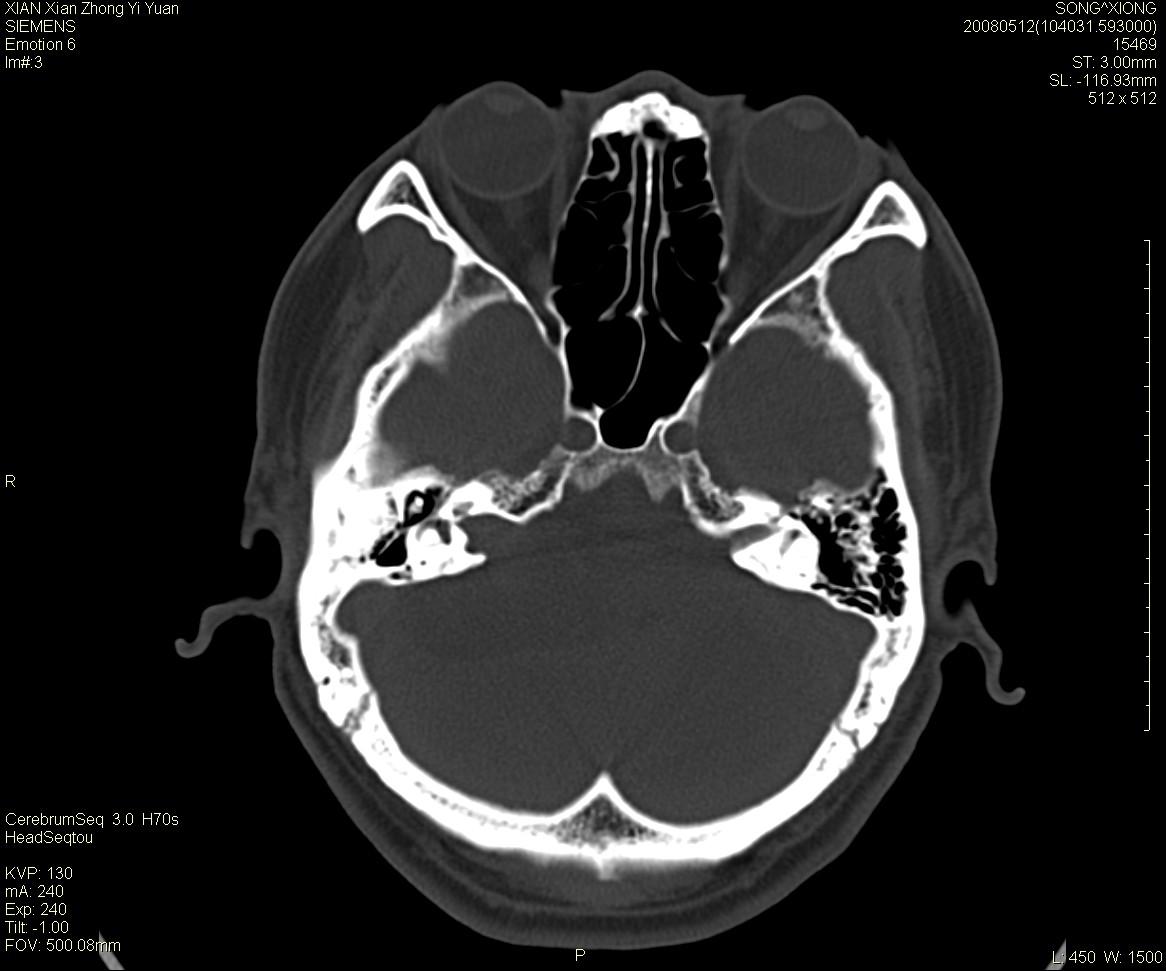

右侧内耳道慢性增宽,内耳道口出可见稍高密度影,桥小脑角池可见以较大低密度影,内缘较清,小脑、脑干、第四脑室受压、移位。

考虑:听神经瘤。

骨窗显示内听道扩大,考虑右侧听神经瘤